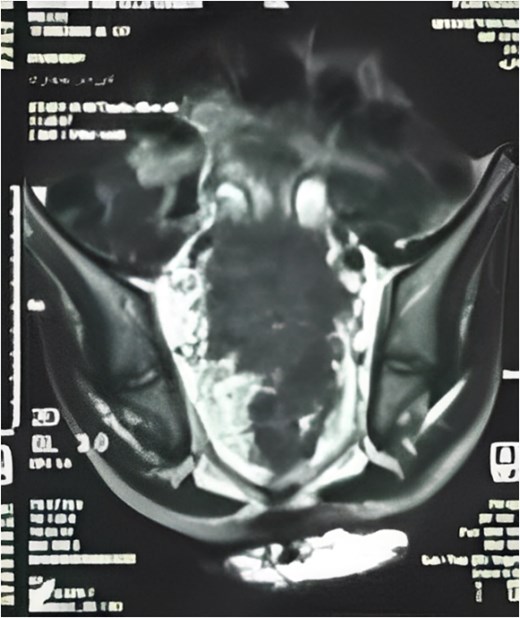

Pelvic MRI (Fig. 2) identified a 5.5 × 5.5 cm rectal mass invading the posterior wall, extending to the upper rectum and rectosigmoid junction, and encasing both ureters. Enlarged mesorectal lymph nodes and extramural vascular invasion were also observed. A CT scan of the chest, abdomen, and pelvis showed no distant metastases.

MRI sagittal view showing the tumor extending from the rectosigmoid to the upper and middle rectum, with mesorectal lymph nodes and extramural venous invasion.